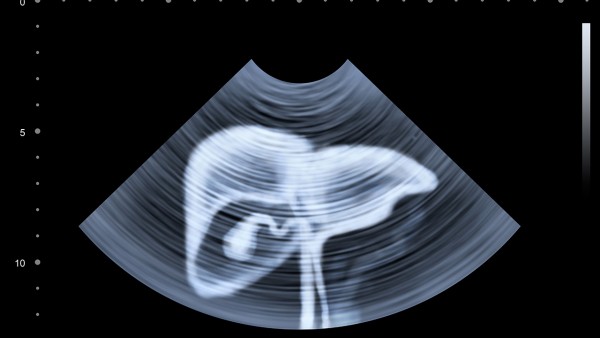

在怀孕的过程中,定期的孕检有时候是需要进行B超检查的,主要是观察胎儿的发育情况,并且检查是不是发生了异常情况。但是,有些孕妇听说,做B超对胎儿会有一定的影响,就很害怕对孩子带来不利,很关心方面的事项。那么,做B超对胎儿影响大吗?

在人体的多数器官中,损伤几个细胞无关紧要,但如果是损害了生殖细胞或处于发育敏感阶段的胚胎,则其后果是严重的。所以,孕期做B超尽量不要超过3次。早孕期间做妇产科B超对新生儿有一定影响,而妊娠中晚期做过妇产科B超的新生儿未见不良影响。早孕期的妇产科B超检查应该谨慎使用。

在很多情况下是需要进行B超检查的,做B超对胎儿影响大吗?很显然,B超对孩子是有一定影响的,不过只要把握好时机还是能够能够降低可能的伤害的。如果担心B超会影响到孩子,可以选择彩超的方式,这是一种非常安全的方式,不用太多的担心。